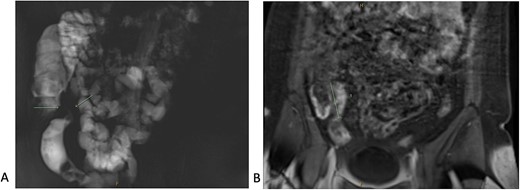

The patient proceeded to an elective laparoscopic ileocolic resection with a side-to-side stapled anastomosis. Macroscopically, there was a stricture of the proximal ileum with associated small bowel wall dilatation and ulceration and cobble stoning of the terminal ileum. Histopathology confirmed stricturing CD—with acute on chronic inflammation, fissuring ulcer formation, reactive epithelial hyperplasia, chronic inflammatory change and smooth muscle hypertrophy (Fig. 3). A second distinct stricture confirmed an endometriotic deposit in the muscularis externa and submucosa with associated haemosiderin-laden macrophages (Fig. 4). This was an unexpected finding of endometriosis in the terminal ileum, as there were no apparent endometrial deposits elsewhere at the time of laparoscopy.

Histopathological findings in endometriosis; (A) H&E section (×20 magnification) showing endometriotic foci (arrows) within the muscularis propria, terminal ileal mucosa is seen in the top right corner; (B) H&E section (×100 magnification) showing a magnified view of an endometriotic focus which comprises of ectopic endometrial glands (yellow arrows) surrounded by ectopic endometrial stroma (black arrows); focal haemosiderin-laden macrophages are also present in the background of ectopic endometrial stroma.